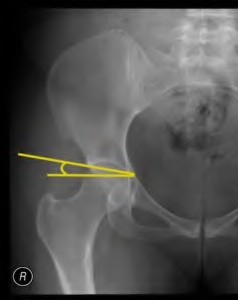

A 72-year-old female presents with progressive left thigh and knee pain for the last year. 5 years ago she sustained a femoral neck fracture treated with the implant seen in Figures A-C (current radiographs). The thigh pain is worse with weight-bearing. C-reactive

protein and erythrocyte sedimentation levels are within defined limits. Which of the following is the most likely cause of her pain?